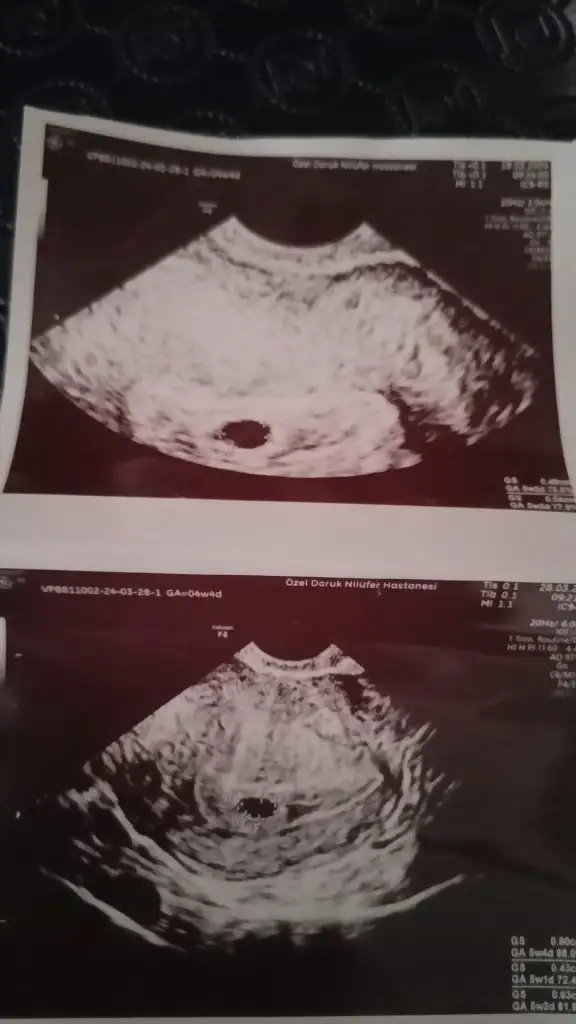

Benimde aşırı kanamam olunca acile gitmiştim ordaki aferdersiniz gerizekalı bana kesesi bozulmuş gibi sagliksizdir bu düşük yaparsın dedi beni kahretti o gece sabaha kadar uyumadım sabah direk özel prof gittim kesesi gayet normal dedi aynen senin gibi 5+4 galiba bak ultrason resmini de aticam

Senin gene iyi o dönem yolk sac ve bebek görülmüş benim sadece kese vardı moralini bozma bana kendi hemsirem WC harici kalkma demişti 3 gün yattım benBilmiyorum kesede biraz bozulma var dedi bekliycezdedi igne yapdi bi tane proluton bi de progestan fitil yazdi sabah aksam bekliycez dedi dusede bilir bebek buyudukce duzelede bilir dedi yolk sac ve embiryo gorundu ama kesede biraz bozulma var dedi bilmiyorum hayirlisi Allahdan dua etmekden baska yapabilcem bise yok umarim duzelir

Bak canım bana gittiğim özel prof dedi bu ultrason cihazını hareket ettirdikce onun görüntüsü değişir benim sonraki ultrason resmim yamuk yumuk birşey sen bol bol su iç dinlen bak bebeğin görünmüş bebeğe genetik pgt yapıldı mıHayir özele gittim cnm bak bu benim kese senin daha duz duruyo sanki baksana

Bak nasıl yamuk duruyor ama hareket ettirdiği için ultrasonda ben görmüştüm mesela yuvarlakti burda bir tuhaf bebeklerimUmarim bise olmaz kanam bida olmadi ama kesenin bozulmasina sasirdim proluton igne yapdi progestan fitil yazdi sabah aksam bekliycez dedi umarim bise olmaz duzelir